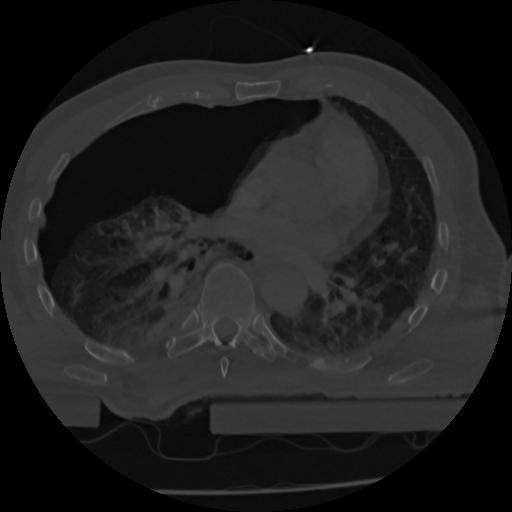

22 ANGIO,CE,Vol,0.5,ANGIO,,